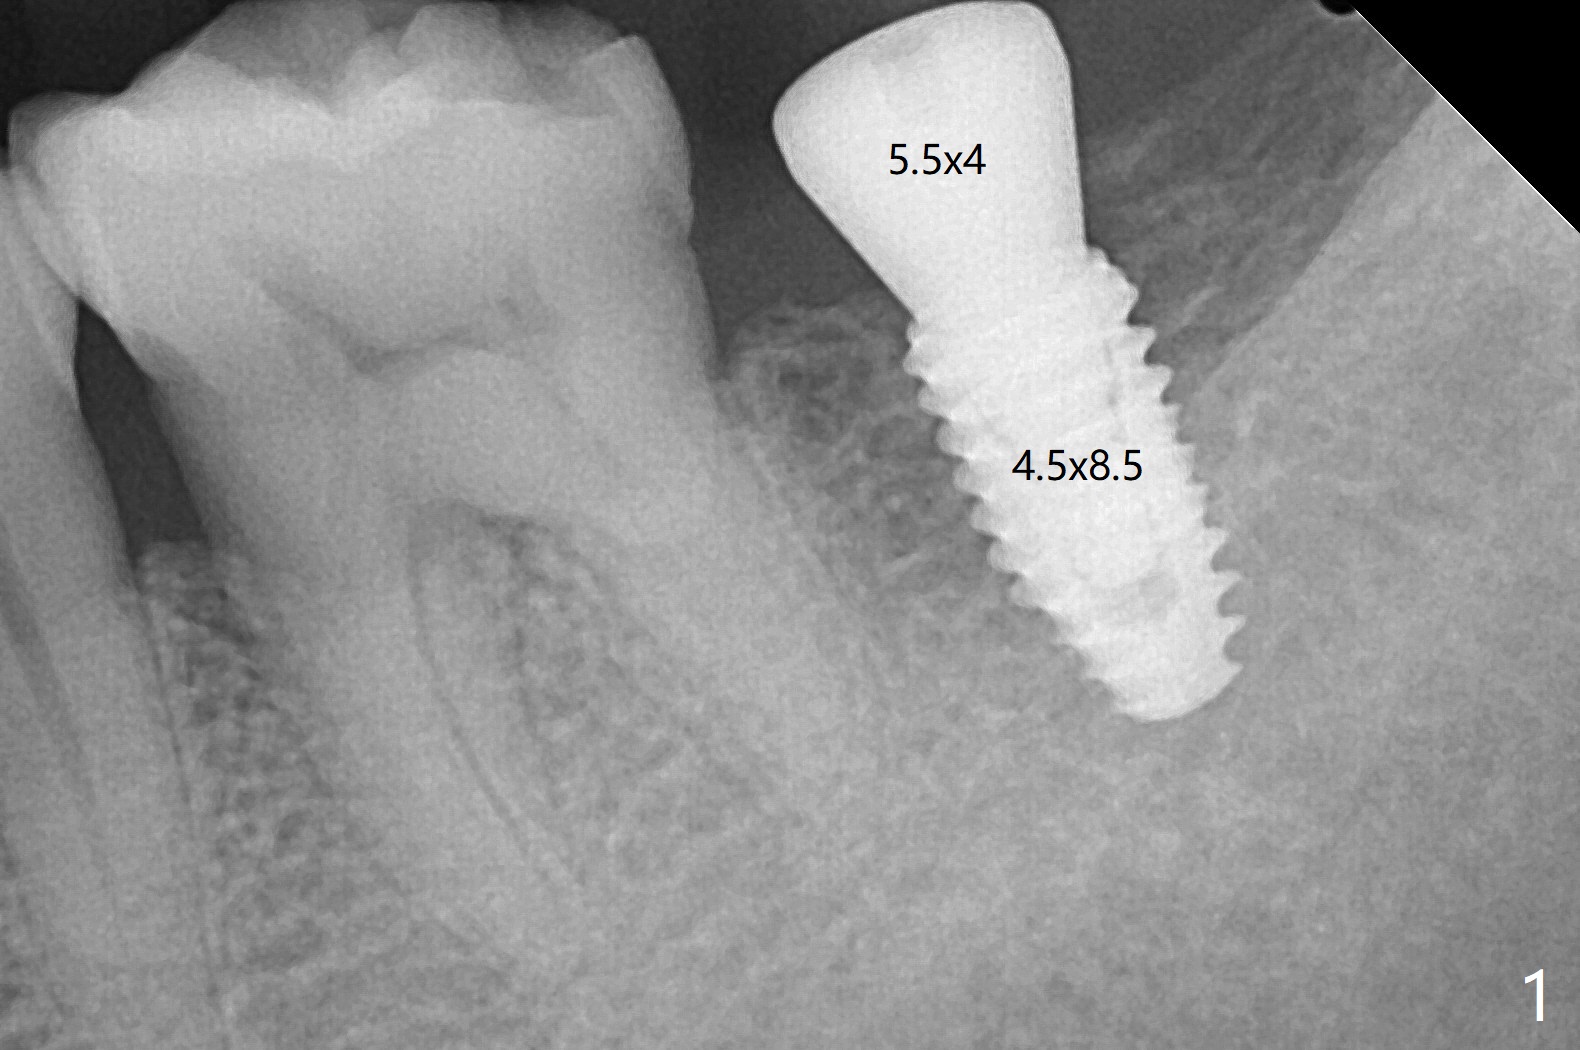

在第二磨牙种植,尤其是男子,咀嚼肌特别发达,为了把钻头放置于导板金属圈(10.5毫米offset),需要磨低对合牙牙尖。如果使用9毫米offset,植体位置方向欠缺些,钻洞就方便些。